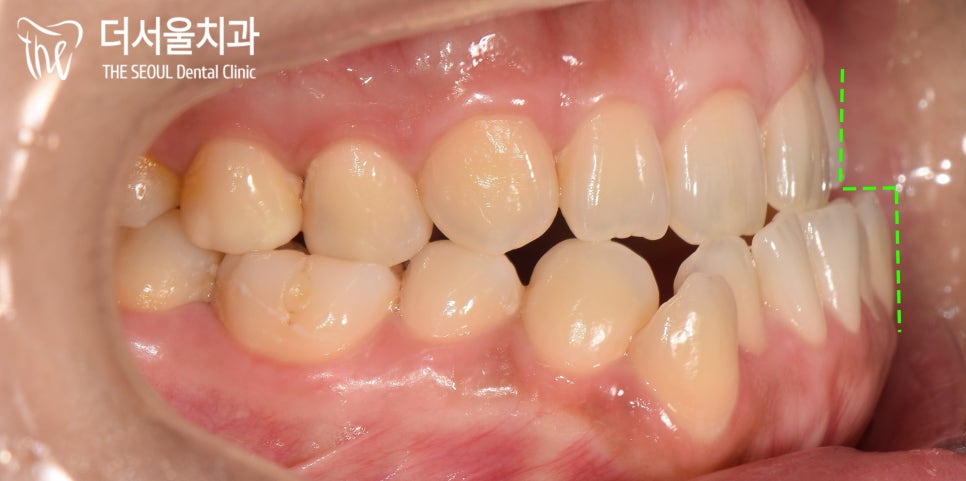

『현재 상황은?』

육안으로 구강 상태를 확인했습니다.

위턱에 비해 발달한 아래턱으로

Class 3급 부정교합을 갖고 있었습니다.

주걱턱이 심하게 나타나 있는 것이 관찰되네요.

그로 인해 상, 하악이 거꾸로 물리는

반대교합이 나타났으며

입이 다물어지지 않고 있었는데요.

생활이 꽤 불편하셨을 거라 생각이 듭니다.

이런 경우에는 절단 기능을 아예 하지 못하기에

끊어 먹는 것을 아예 할 수가 없게 되죠ㅜㅜ